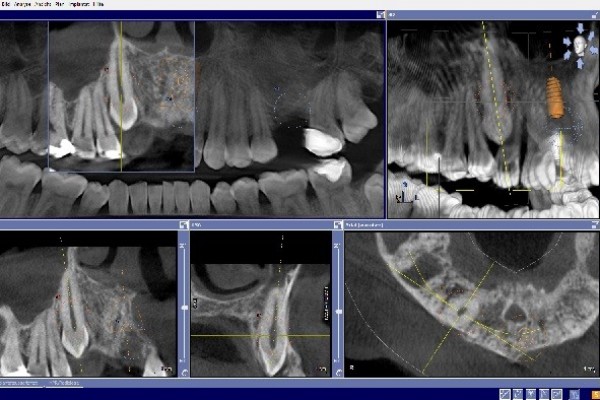

Mit der Digitalen Volumentomographie (DVT) bieten wir unseren Patienten ein hochmodernes dreidimensionales Diagnoseverfahren, welches eine deutlich besseren Bildqualität, erhöhte Sicherheit für Patient und Behandler sowie eine geringere Strahlendosis als bei einer herkömmlichen CT bedeutet .

Die DVT arbeitet mit Röntgenstrahlen. Wie auch die Computertomographie (CT) können mit der DVT hochauflösende Schnittbilder erstellt werden, diese haben jedoch eine deutlich bessere Auflösung. Hierdurch ist eine noch genauere Diagnose und spätere Therapie möglich.

Die Röntgenröhre produziert zweidimensionale Einzelaufnahmen, die von einem Hochleistungsrechner zu einem dreidimensionalen Datensatz umgerechnet werden.

Innerhalb kürzester Zeit wird so direkt eine präzise Diagnosegrundlage erstellt, der wir alle Informationen entnehmen können, die wir für Ihre Therapieplanung benötigen.

• Implantatplanung in der 3D Simulation

• exakte Positionierung von Implantaten

• Einschätzung des Knochenangebots und der Knochenbeschaffenheit vor der Implantatversorgung